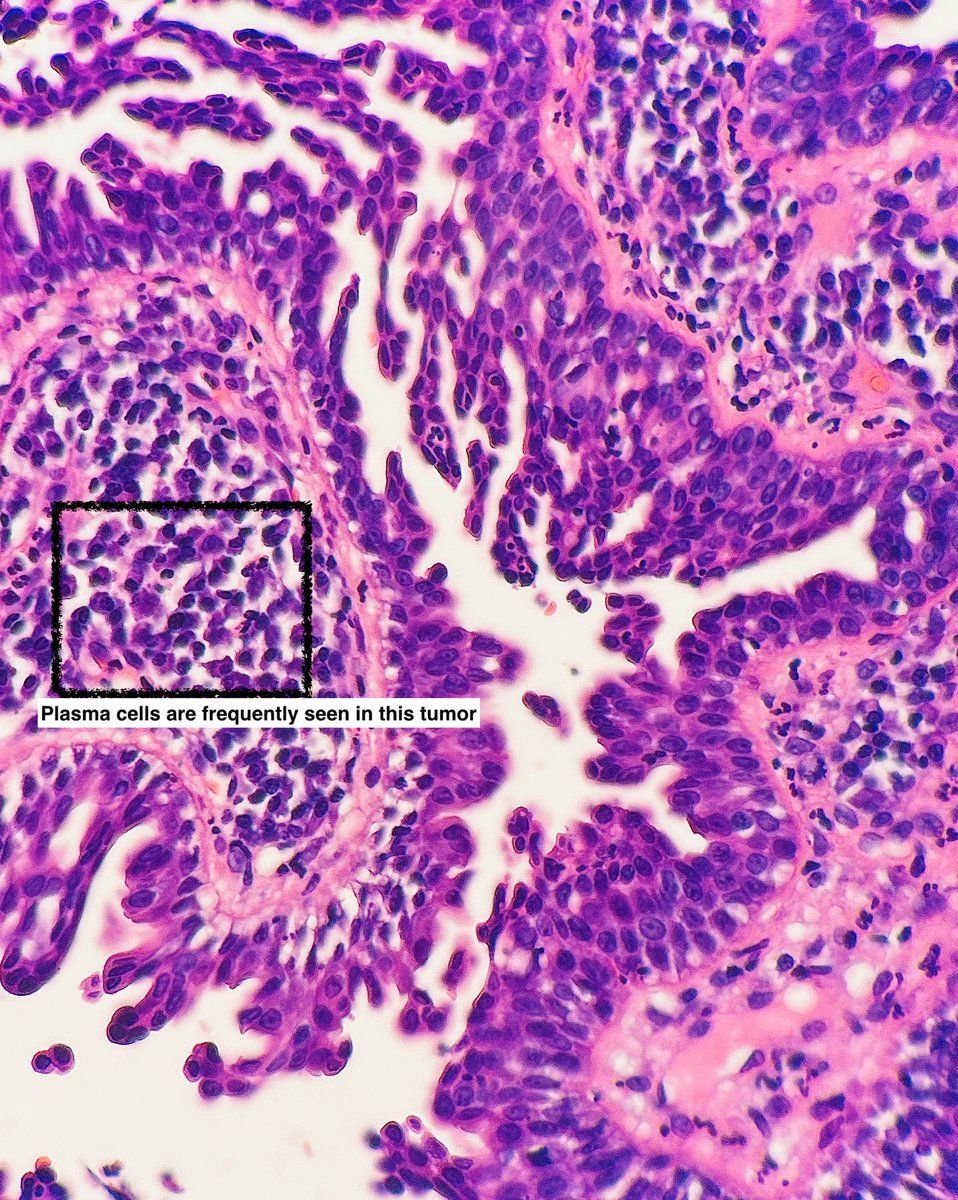

I am a benign, rare adnexal tumor I like to be on the scalp/face and may be associated with nevus sebaceus You may see a lot of plasma cells in me Who am I? 🤔 #pathx #dermpath #fammed #medx #path4people #pathagonia

Path4People's tweet image. I am a benign, rare adnexal tumor

I like to be on the scalp/face and may be associated with nevus sebaceus

You may see a lot of plasma cells in me

Who am I? 🤔